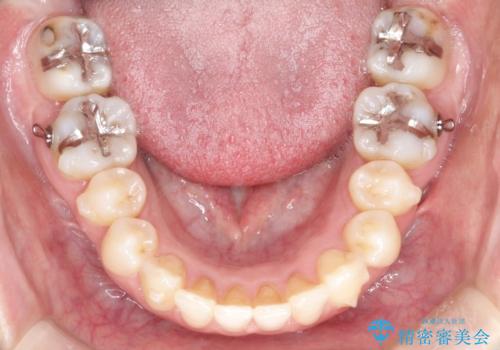

初診時の歯並びの状態としては、上下ともに前歯部の中等度のがたつきがあり、特に左上の前歯が1本内側に入り込んでしまっている状態でした。

内側に入り込んでしまっている歯を出してくることに非常に時間がかかりましたが、一度歯を歯茎の方へ押し込みそして前へ出してくる2段階の治療を行いました。

見た目、嚙み合わせ及び、治療期間や施術内容に大変ご満足いただきました。